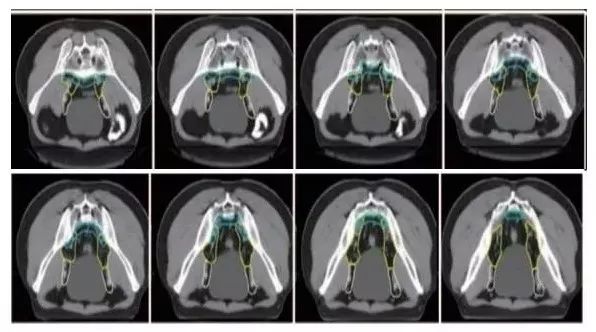

a. 骶前区:骶骨前方区域,包括腹部骶前区⁃PS S (青色) 和盆腔骶前区⁃PS (淡蓝色)(2B 级证据);

b. 直肠系膜区:由全部直肠系膜区以及直肠系膜筋膜组成⁃M(深绿) ;

c. 髂内淋巴引流区⁃LLN P (黄色);

d. 闭孔淋巴引流区⁃LLN A (紫色);

e. 髂外淋巴引流区⁃EI (灰白色);

f. 腹股沟淋巴引流区⁃IN (黄褐色);

g. 坐骨直肠窝⁃IRF (天蓝色);

h. 肛门括约肌复合体⁃SC (桔色)

(b⁃h:1 级证据)。

高危淋巴结引流区及高危复发区边界定义及图谱(CT层厚0.5cm,俯卧位)

勾画图谱